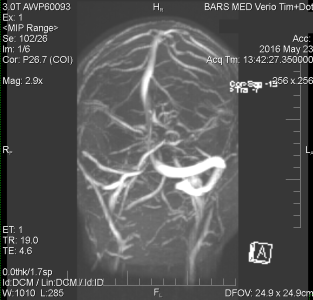

2. Ассиметрия кровотока по венозным синусам.

2. Ассиметрия кровотока по венозным синусам.